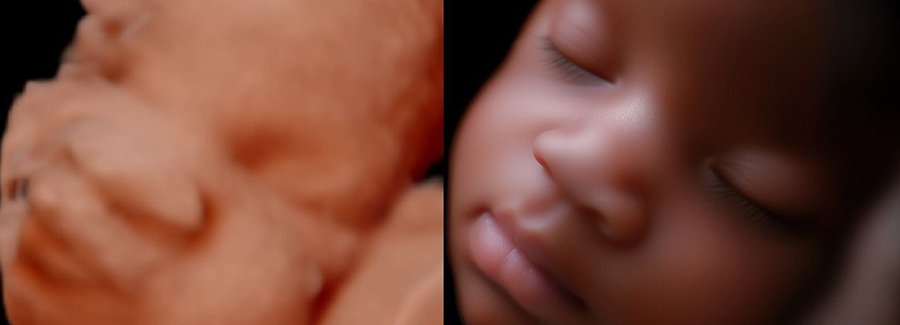

Often referred to as 5D, HD or FRV (fetal realistic view), 5D/HD is the newest development in pregnancy imaging. It captures and combines high definition volume data to create automated images with amazing color and clarity so you can see your baby as though you were looking from inside the womb.